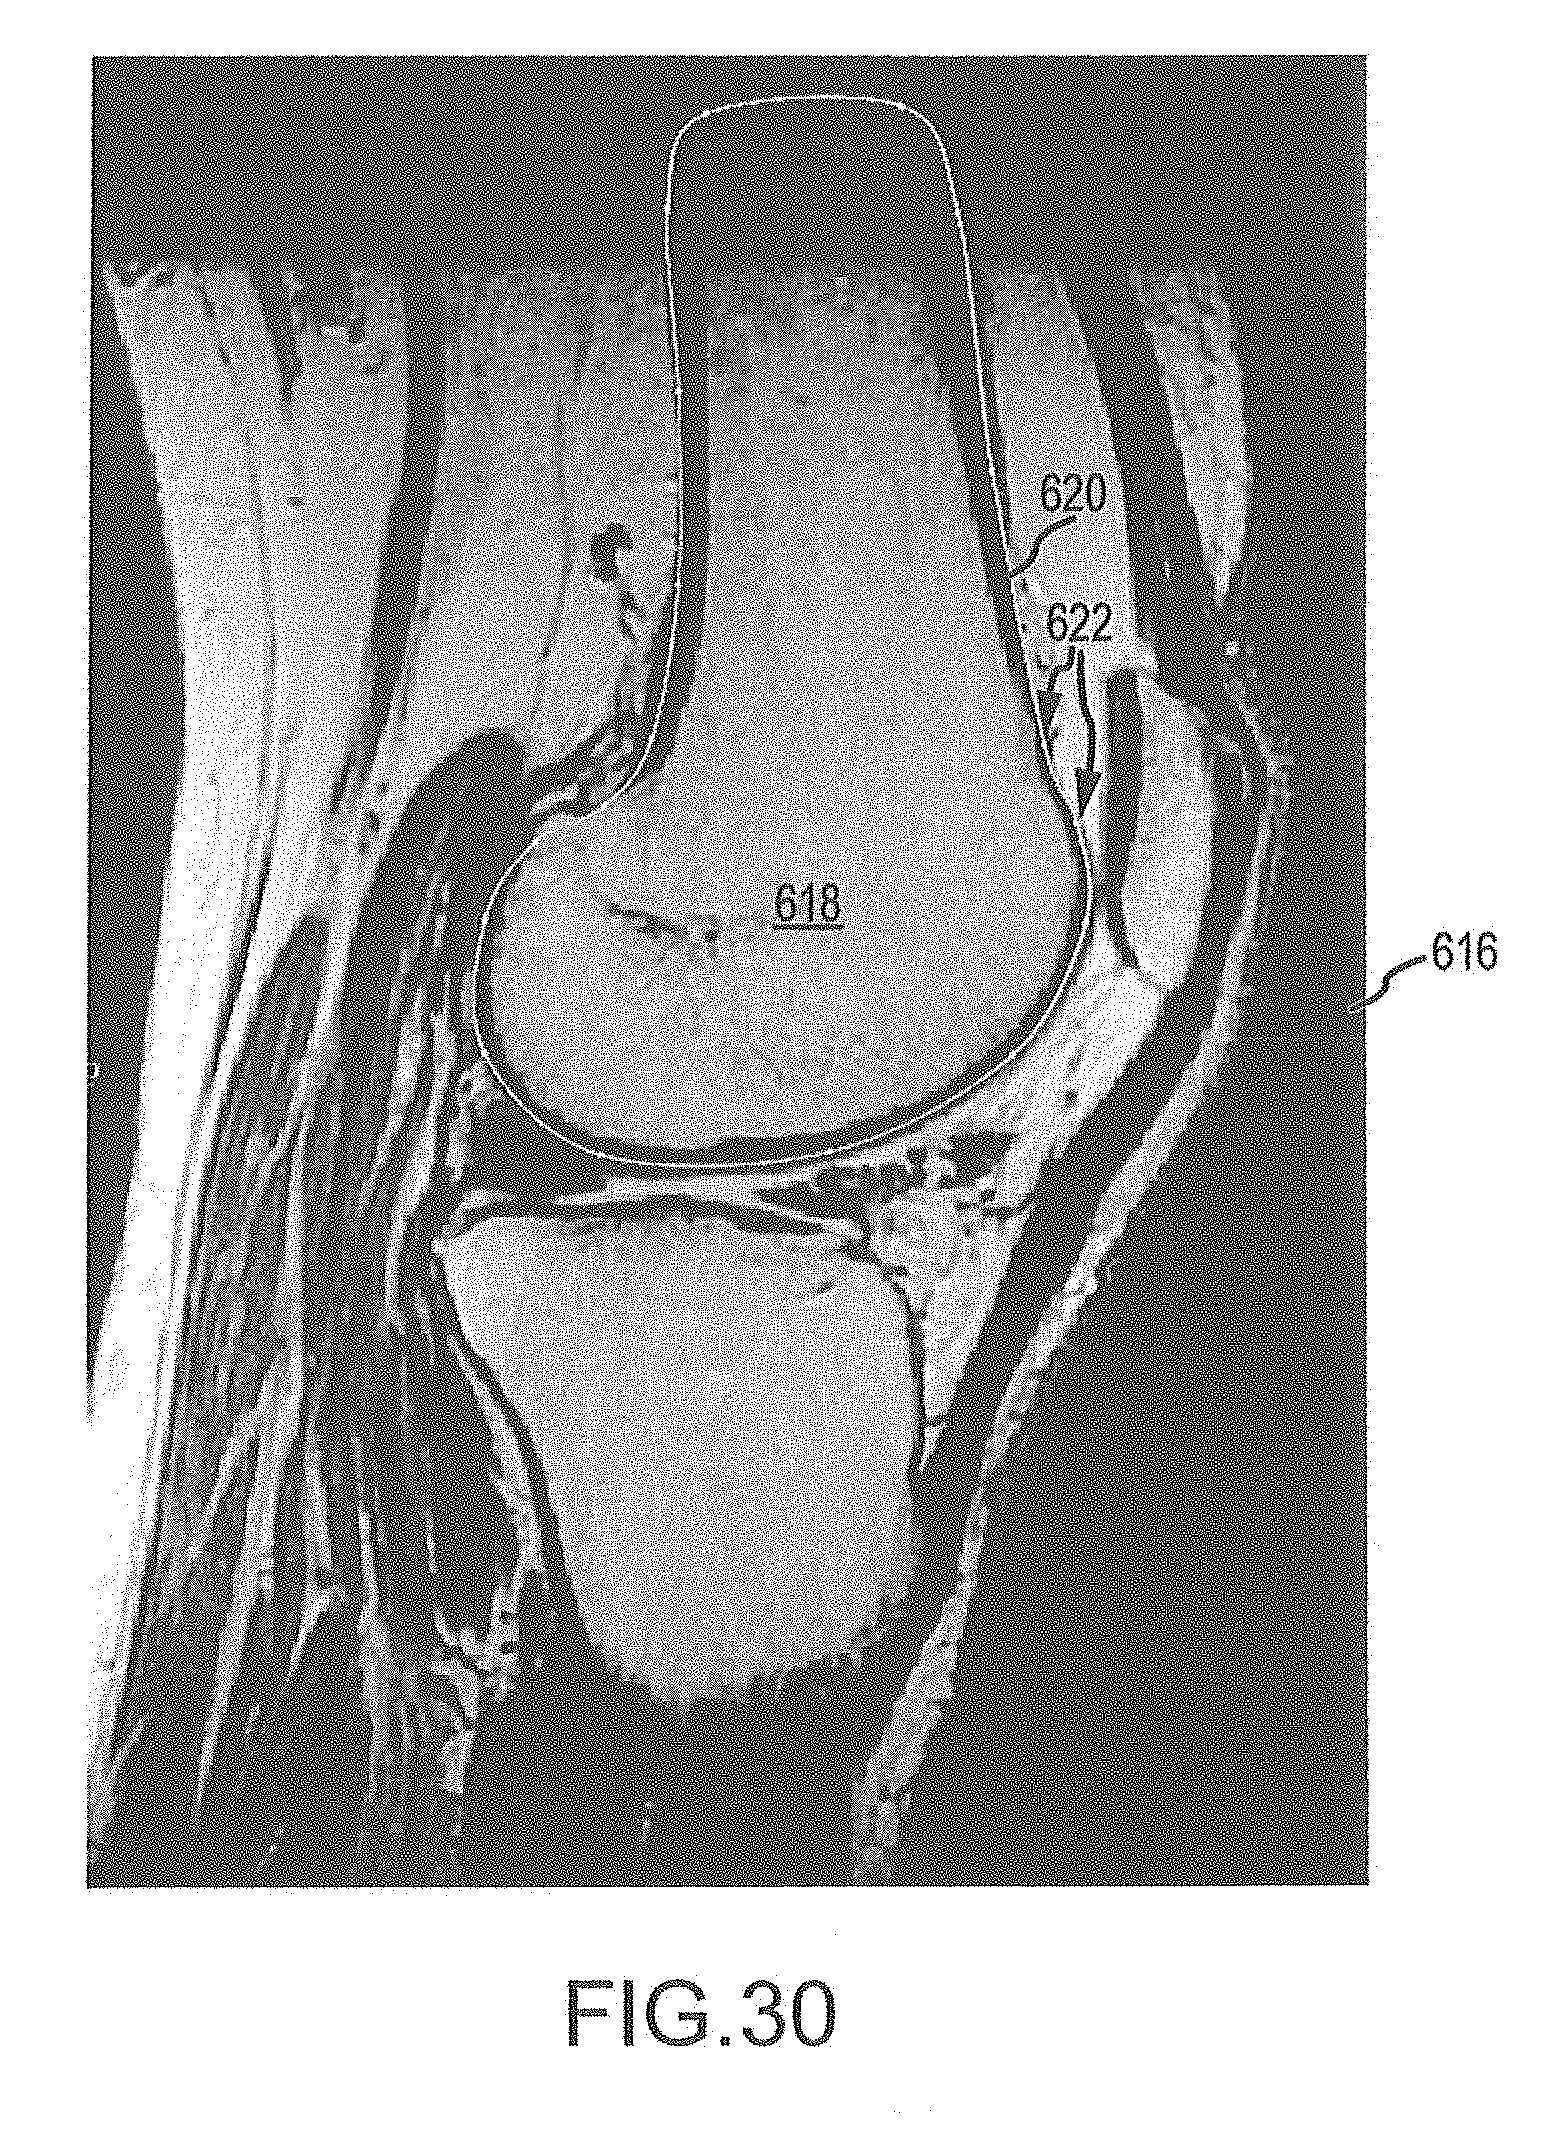

[0087]

FIG. 30 is an image slice of the representative femur to be used to generate a golden femur mesh.

[0088]